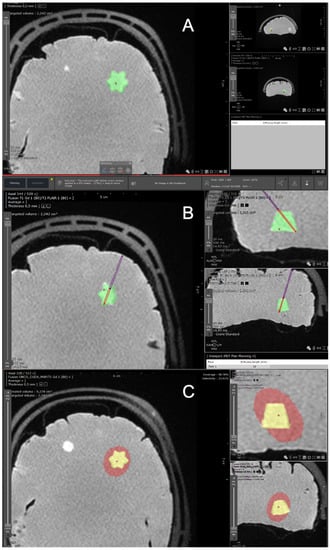

2.1.4. Optical Fibers Positioning

2.1.6. Monte Carlo Simulations

Specifications of the “Mcxyz” Program for Interstitial 5-ALA PDT